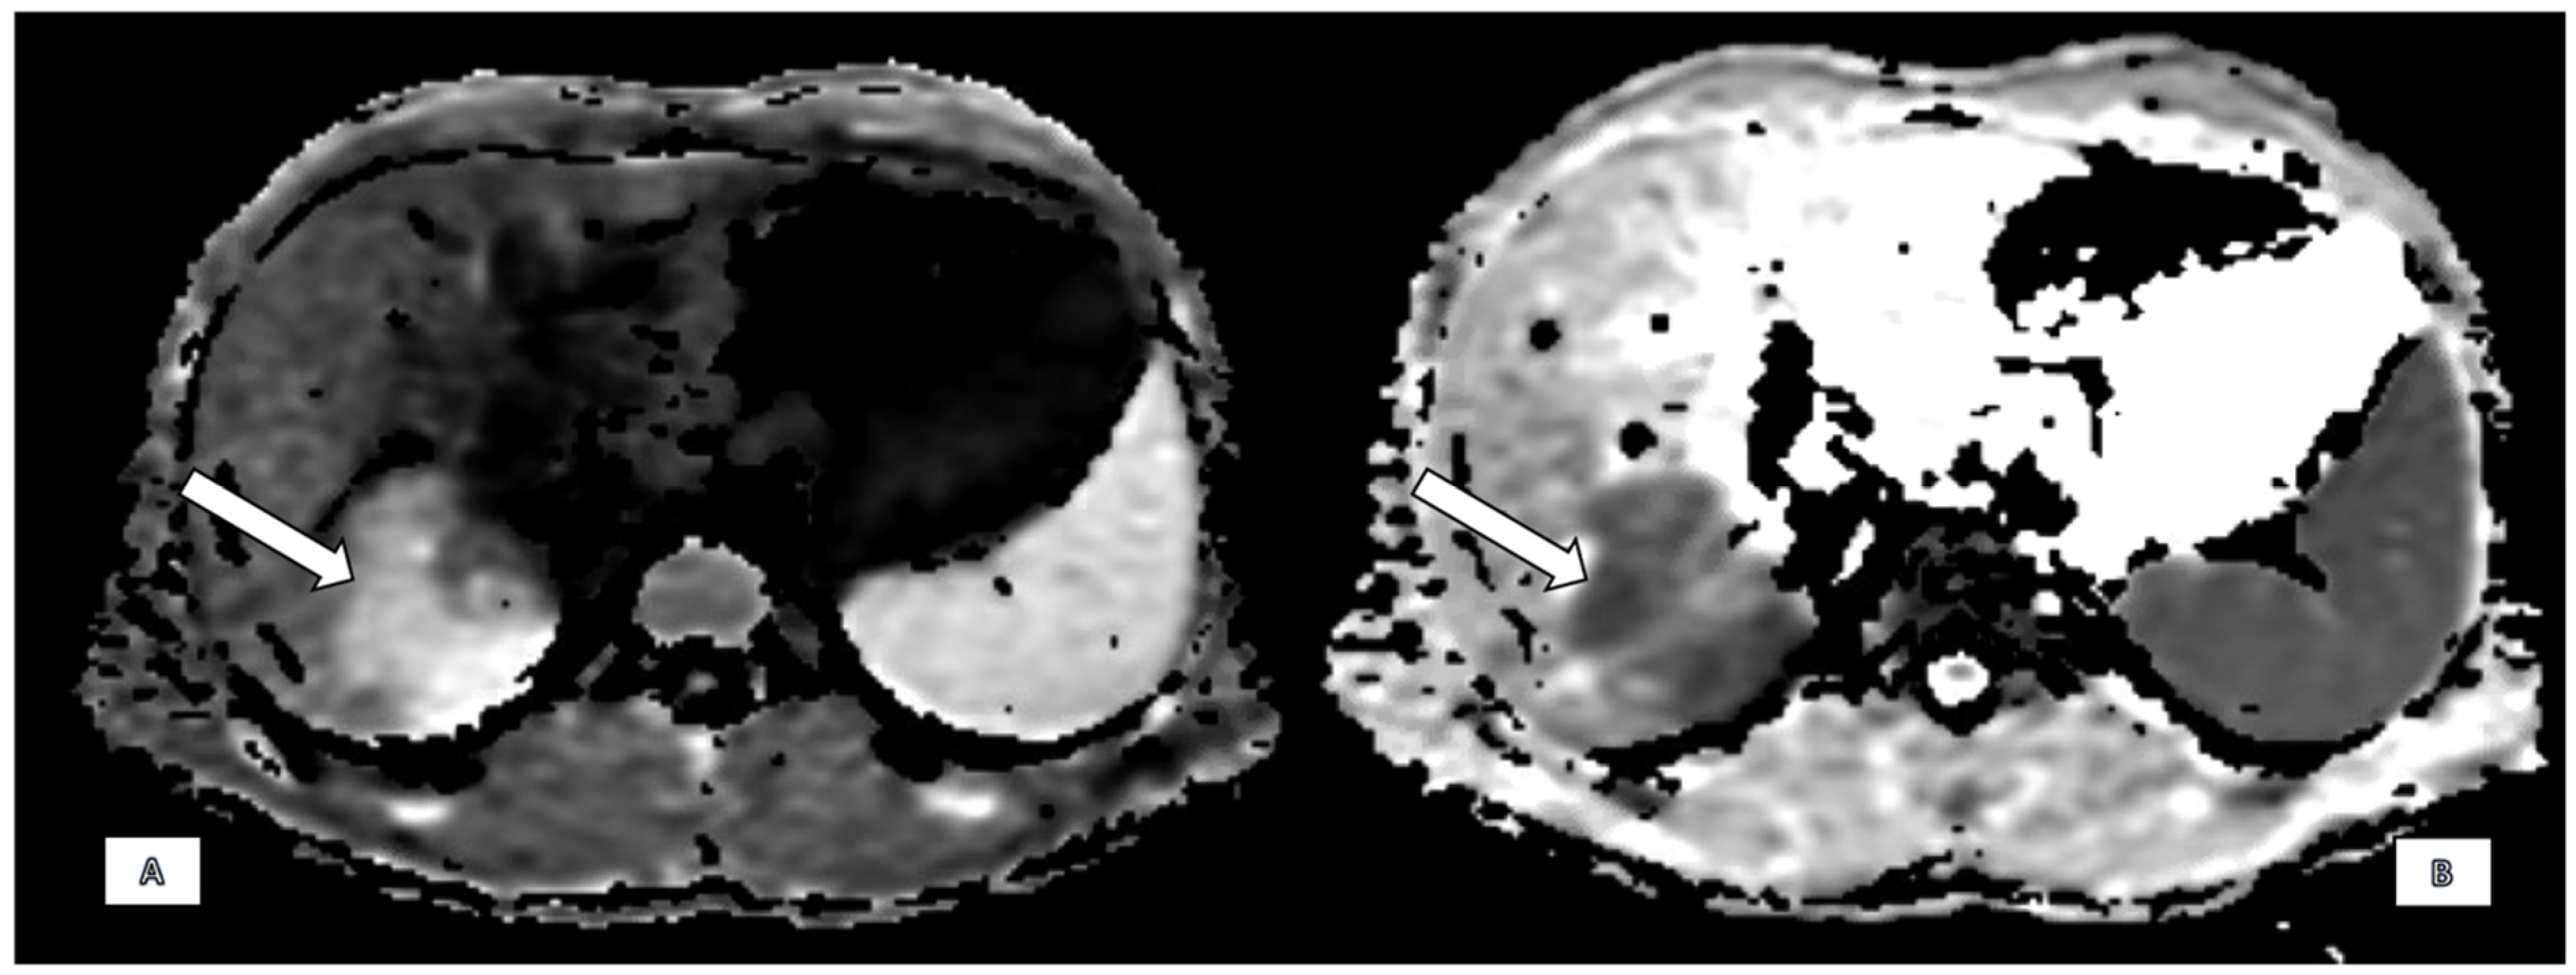

2.2. Imaging